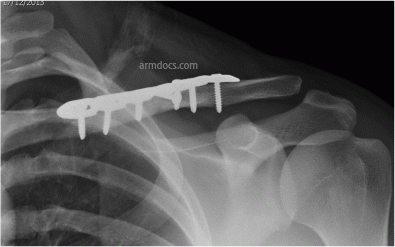

This protocol is applicable to patients treated surgically for a mid-shaft clavicle fracture. Healing of the fracture may take 3 to 5 months.

Clavicle Fracture 1B